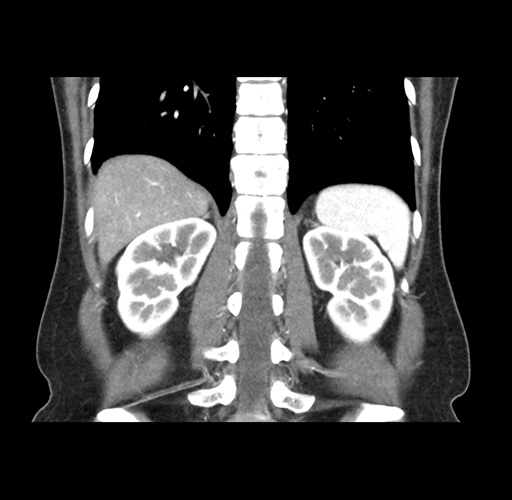

Imaging Analysis

Look through the patient's CT scan to identify any areas of concern for the necessary procedure.

Based on your CT findings, which issue(s) would give reason for "planned slowing down moment(s)" in this case?

Considering a standard left lateral sectionectomy procedure, what step(s) of the operation would you do differently in this case ?